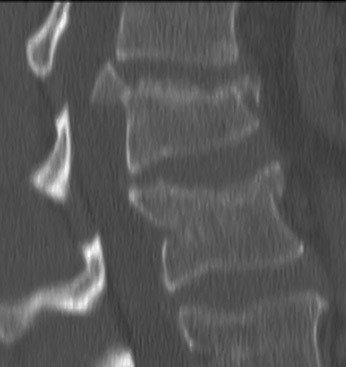

Axiale spondyloartritis

Oa M. Bechterev

Jongeman (30) met geleidelijk progressieve pijn in de rug. Pijn wordt erger in rust en verbeterd bij bewegen. Ochtendstijfheid. Positieve familie anamnese psoriasis. Uveitis anterior in VG.